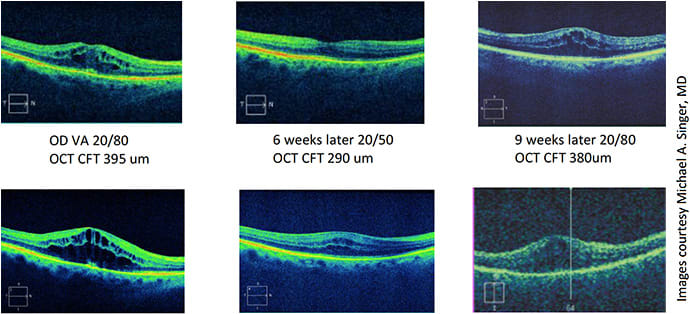

I decided to treat her with bilateral anti-VEGF injections. One injection would last around a month or two, and her vision would improve (20/80 to 20/50 OD and 20/100 to 20/60 OS); however this was short lived, lasting a little more than a month (Figures 1 and 2).